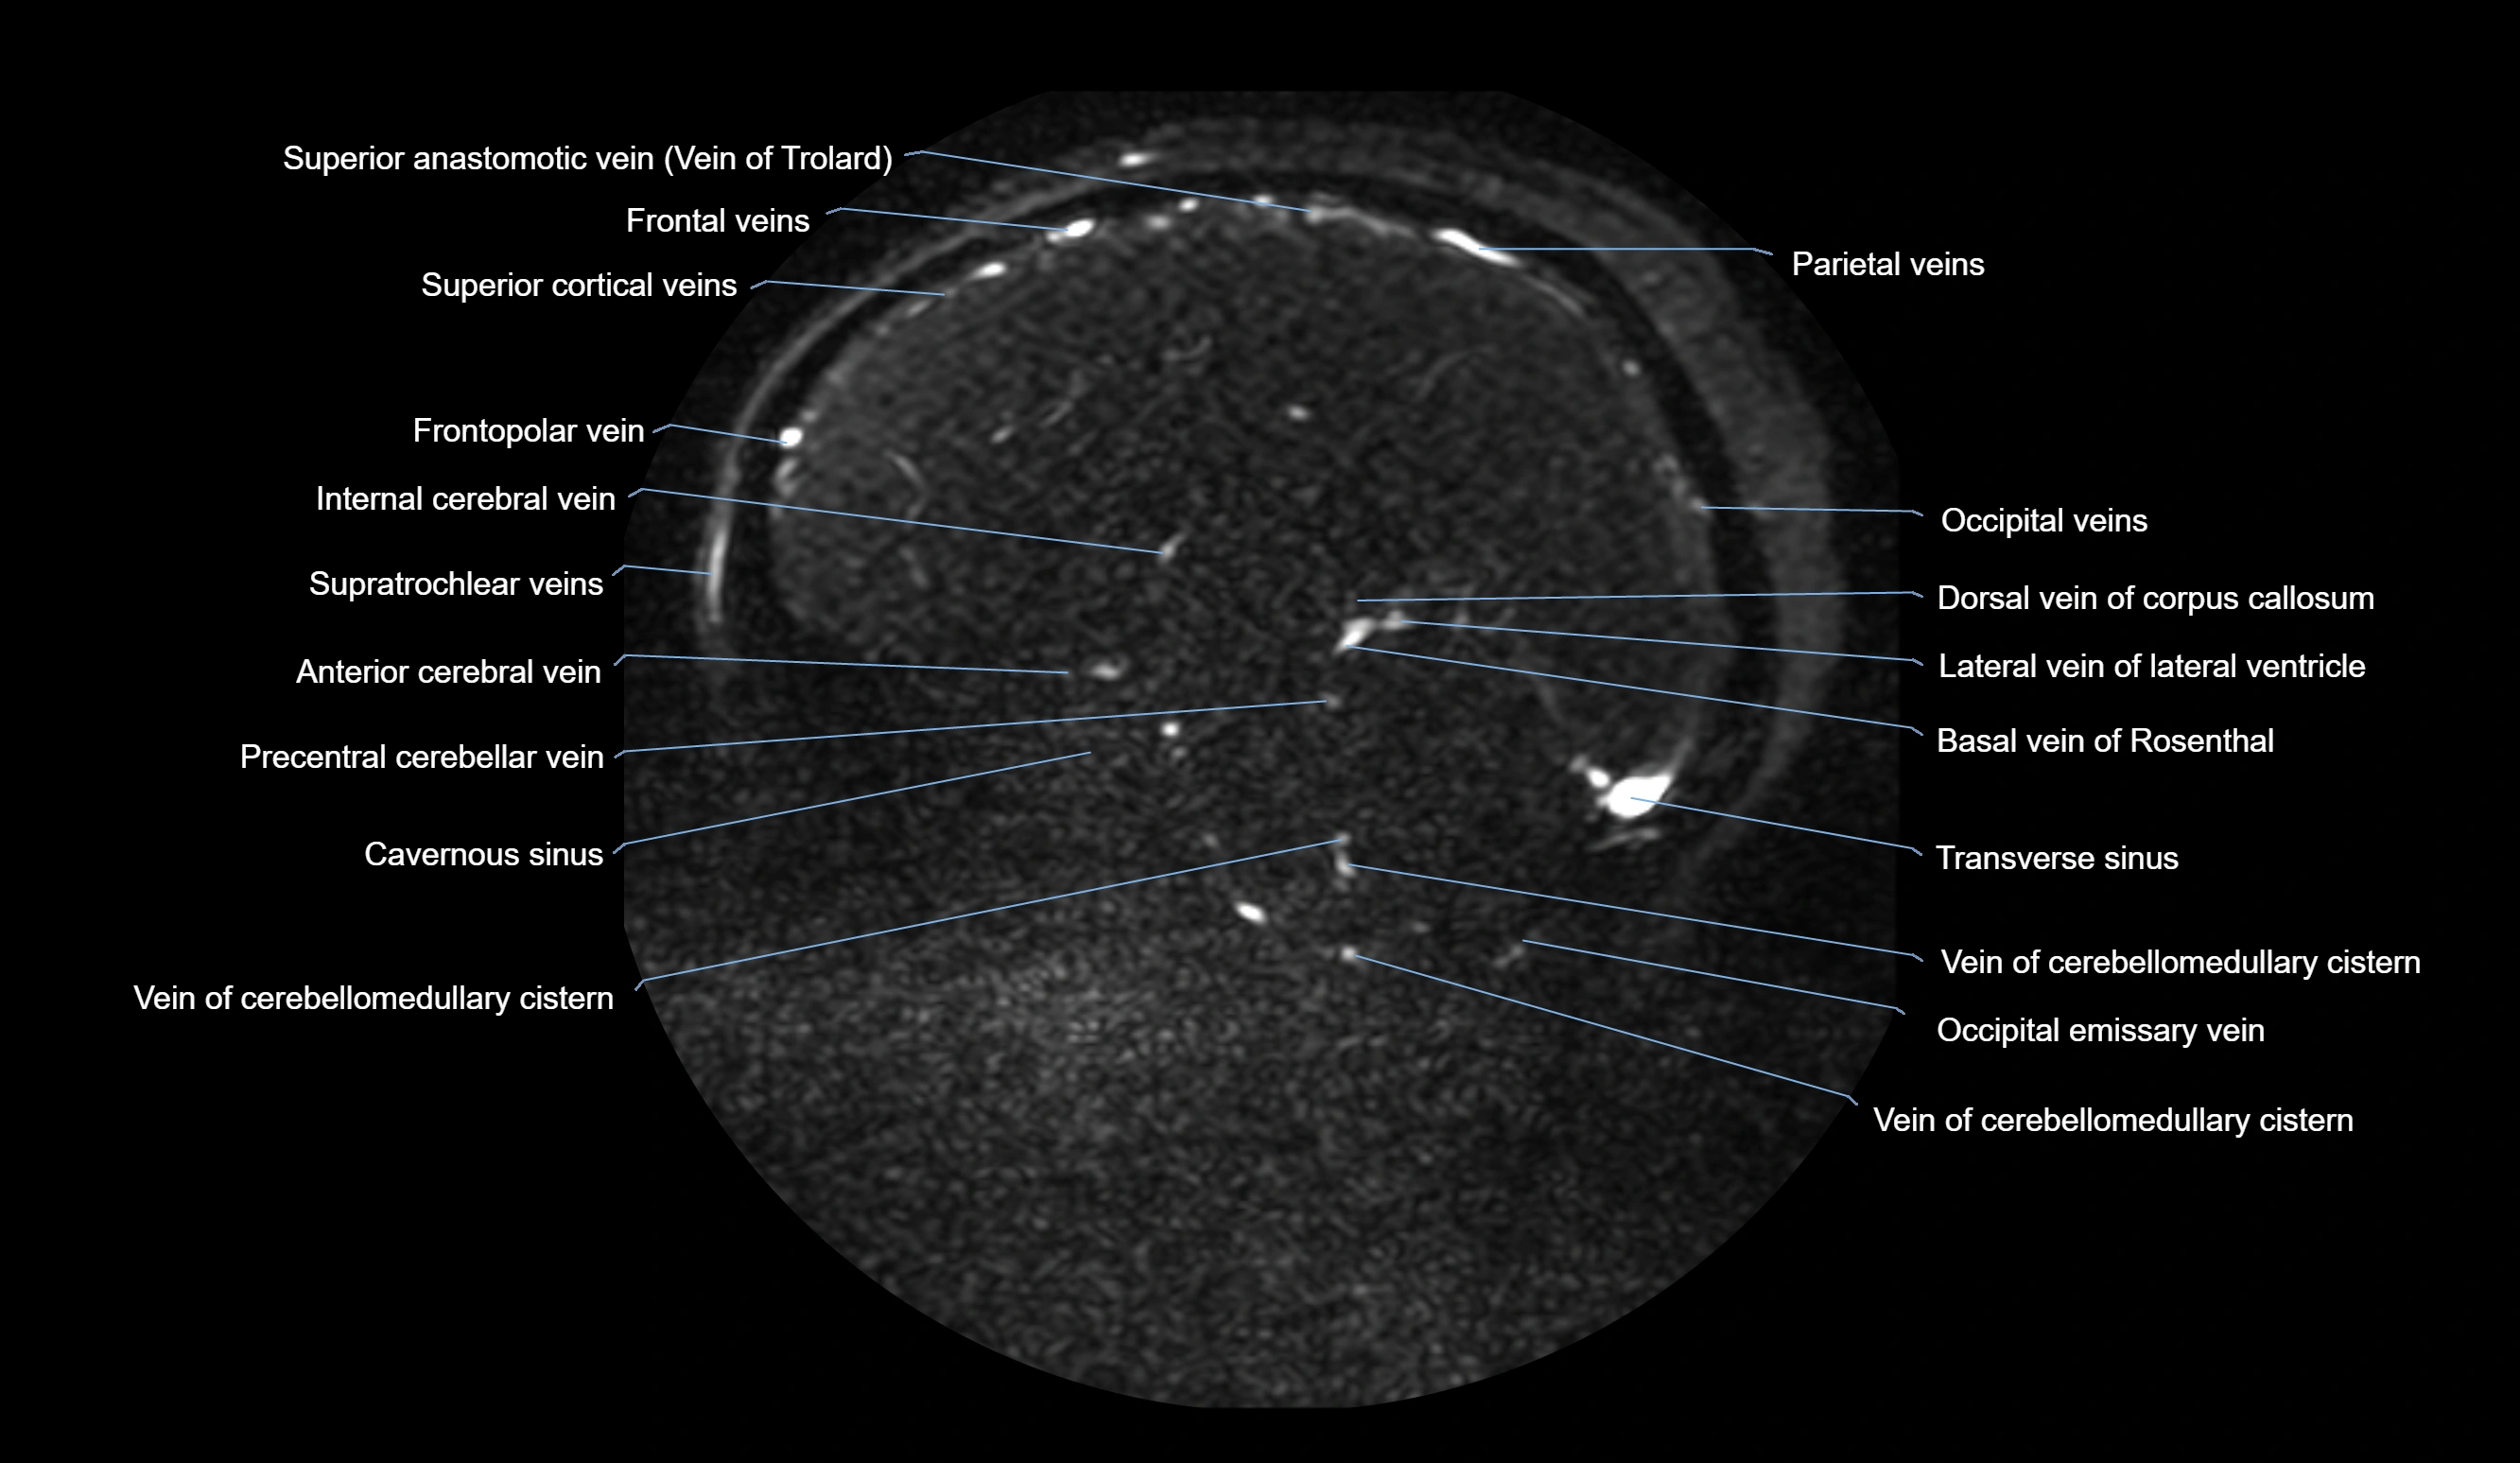

MRI images

image